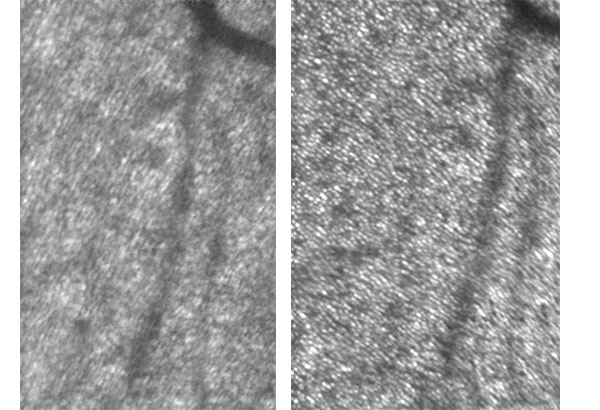

The picture below shows the before (left) and after (right) adaptive optics aberration correction on living human retina. Individual photoreceptor cell (~3µm) is well resolved with the help of adaptive optics.